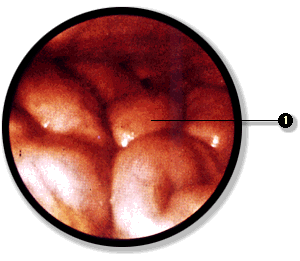

La cavidad peritoneal puede ser explorada directamente mediante la laparoscopía. En este examen se introduce un instrumento óptico, el laparoscopio, y se inyecta gas en la cavidad peritoneal para separa las hojas visceral y parietal del peritoneo. De esta manera es posible recorrer la cavidad e incluso realizar, bajo visión directa, ciertas intervenciones quirúrgicas que no requieren de un abordaje amplio de la cavidad abdominal.